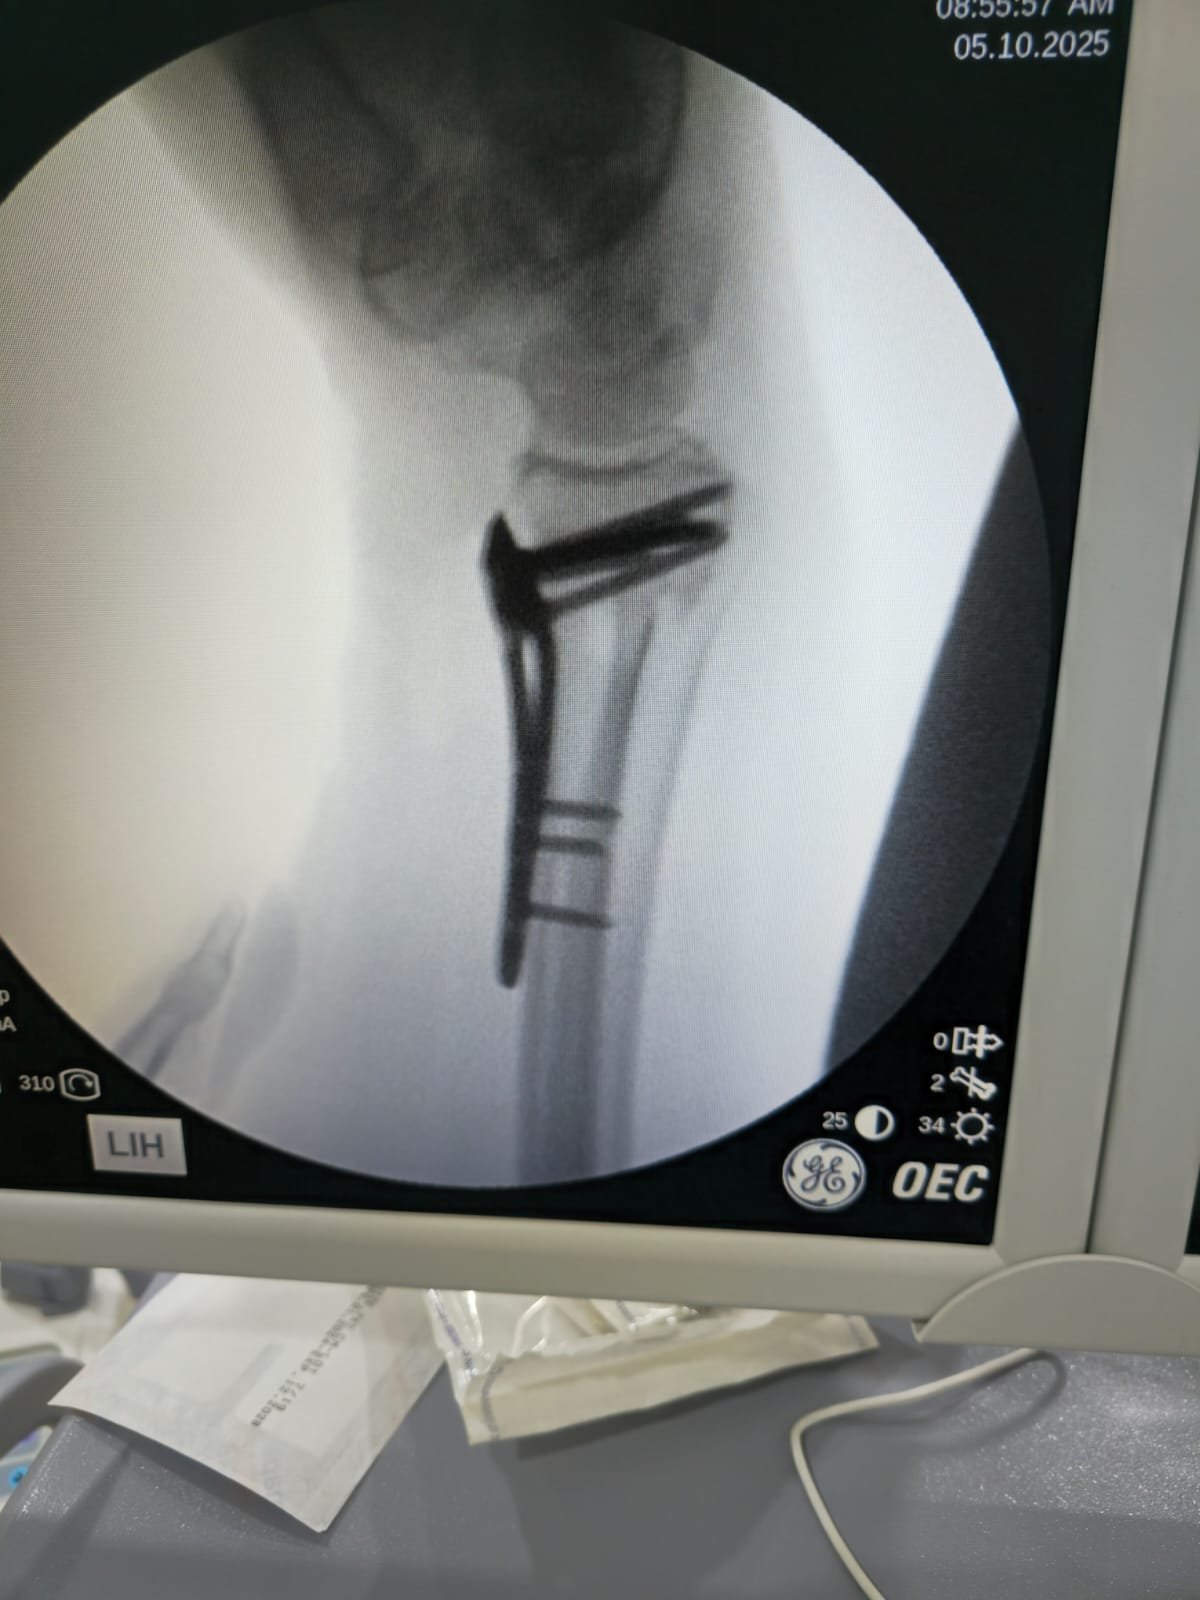

يحدد د. أحمد خطة التعامل مع الكسر أو الرضّ العظمي: فحص سريري وقراءة أشعة، اختيار التثبيت (جبس/جبيرة أو تثبيت جراحي عند اللزوم)، وضبط الألم، ثم متابعة منظمة حتى اكتمال الالتئام.

تشخيص سريع وقراءة أشعة دقيقة في نفس الزيارة.

مواعيد متابعة وصور توثّق تقدّم الالتئام واتخاذ قرار العودة للنشاط.